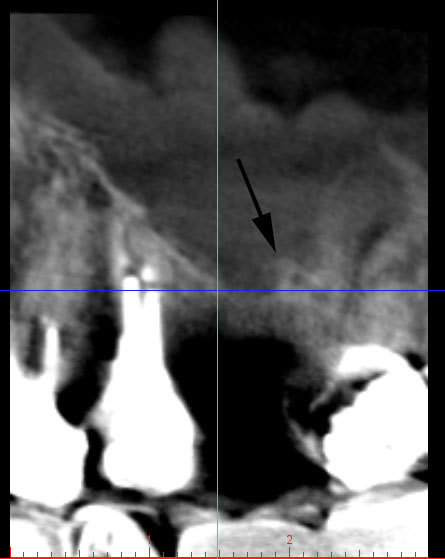

je vais essayer de vous envoyer l'image du scan

-Une dent extraite avec déjà une résorption verticale qui met en danger le contexte parodontale de 25 et 27.

-Une résorption vestibulaire qui sera de plus en plus difficile à traiter sans une greffe d’apposition. Amibien l’a parfaitement bien compris. Dans le cas présent, j’ai fait une ROG pour combler une concavité vestibulaire déjà bien marquée. J’ai mis une membrane plus pour combler cette concavité que pour fermer la fenêtre d’accès.

- Un sinus qui va devenir encore plus procident et qui va avoir encore plus d’expansion.